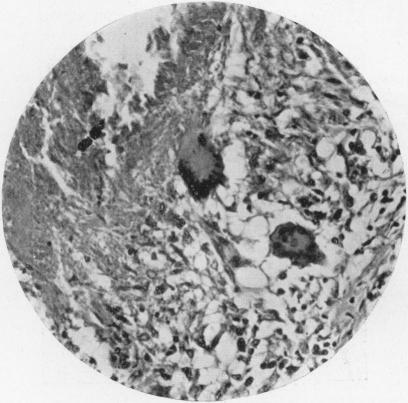

Pulmonary Asbestosis.

Br Med J. 1927 Dec 3;2(3491):1024-5. doi: 10.1136/bmj.2.3491.1024.